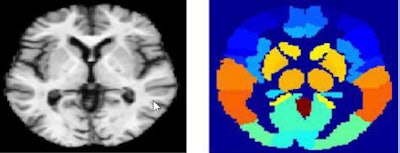

Above, MRI image (left), MRI atlas (right) used for deep learning-based image analysis. Below, PET image (left) and PET atlas (right). Images courtesy of Andrés Ortiz, PhD.This feature extraction process has proved effective as the support vector machine classifier provides good classification results, he added.

The classification methods based on deep-learning architectures are applied to brain regions defined by a technique called automated anatomical labeling (AAL). Gray matter images are divided into 3D patches according to the regions defined by the AAL, and then used to train deep belief networks (DBNs).